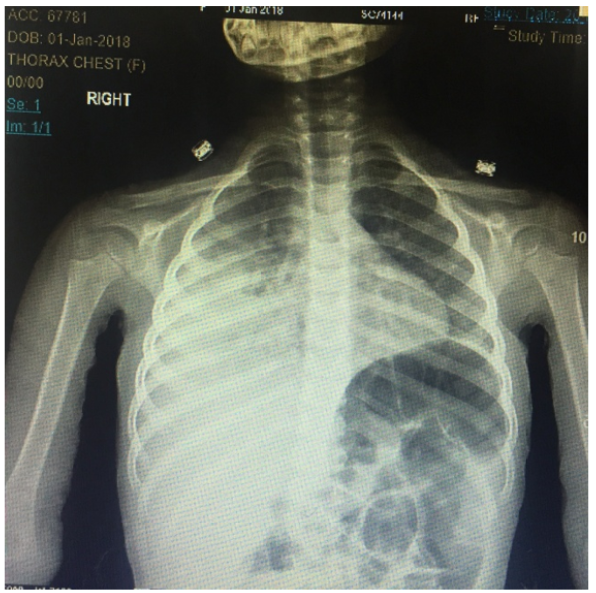

Pneumoperitoneum in an Extremely Preterm Neonate. Can it be an Innocent Finding? Case Report

Mohamed Abouseif Badawi, Mona Khalaf, Ahmad Dana and Anaam R Alhadeethi. 12(2): 19-24.